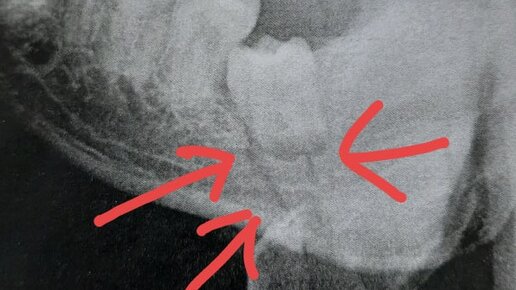

Питание при сломанной челюсти Первые пару дней после перелома для меня были разочарованием, т.к. челюсть ныла при любом повороте или движении, перелом находился в неудачном месте, под зубом мудрости. В...